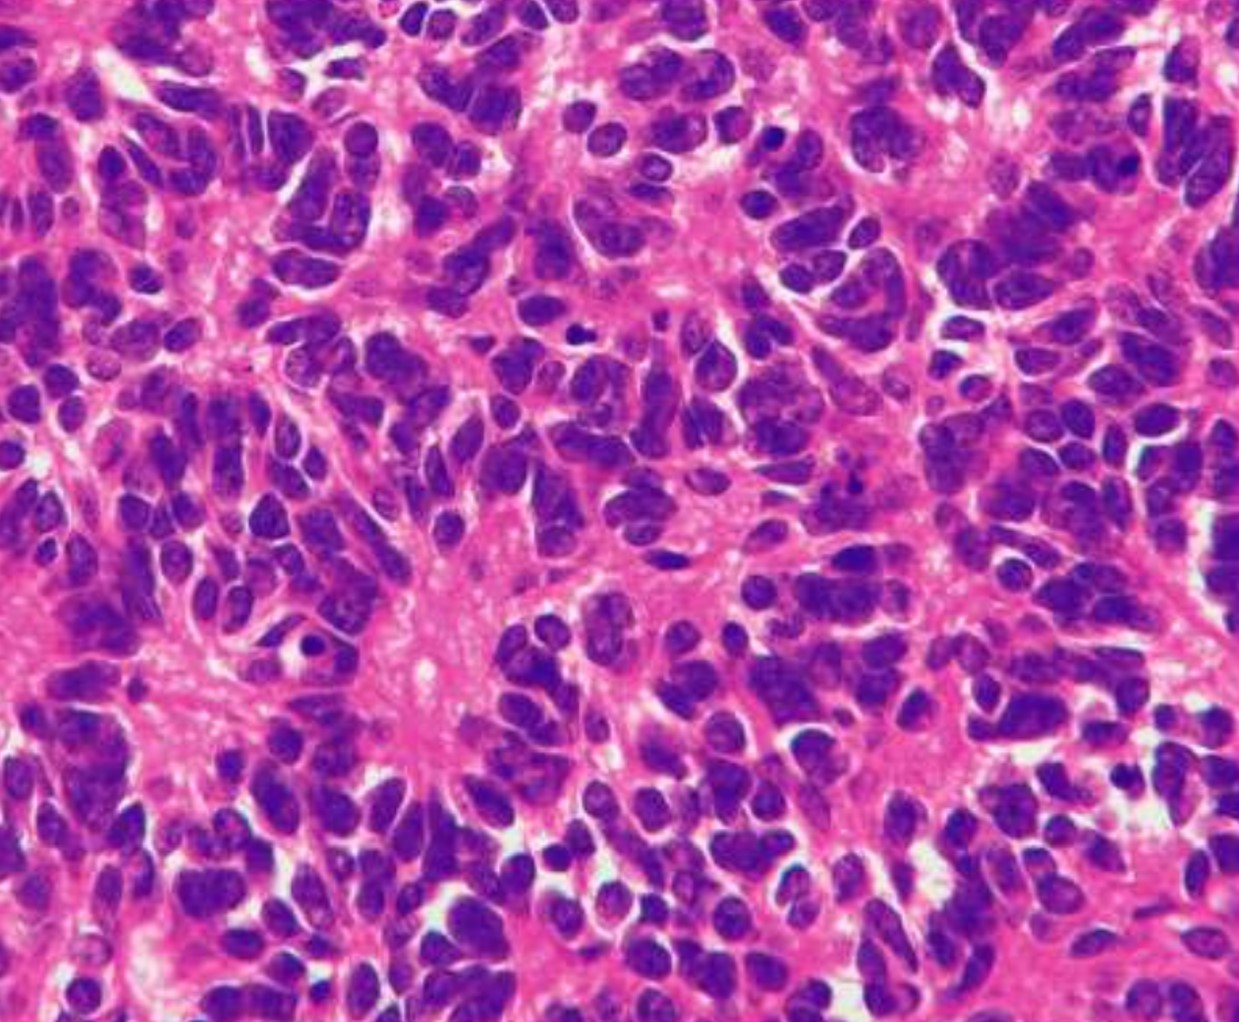

Poorly Differentiated/ Embryonal Tumors

Poorly Differentiated/ Embryonal Tumors

- Malignant small blue cell tumors

- Grade IV

- Young Children

Medulloblastoma

- 20% of pediatric brain tumors

- Posterior fossa

- Spreads by CSF seeding along the subarachnoid space

Primitive Neuroectodermal Tumor

- Supratentorial tumors

- Histologically identical to medulloblastomas, genetically differ from medulloblastomas and peripheral PNET (lack Ewing’s translocations)

- Homer-Wright rosette

Atypical Teratoid/Rhabdoid tumor

- 2% of pediatric brain tumors

- Highly malignant of young children/infants (up to 5 years of age)

- “Rhabdoid” cells

- Multiple lineage markers (epithelial , muscle)

- Molecular Genetics: >90% of cases show loss/mutations of hSN5/INI1 gene on chromosome 22

- IHC: loss of normal nuclear staining for INI1